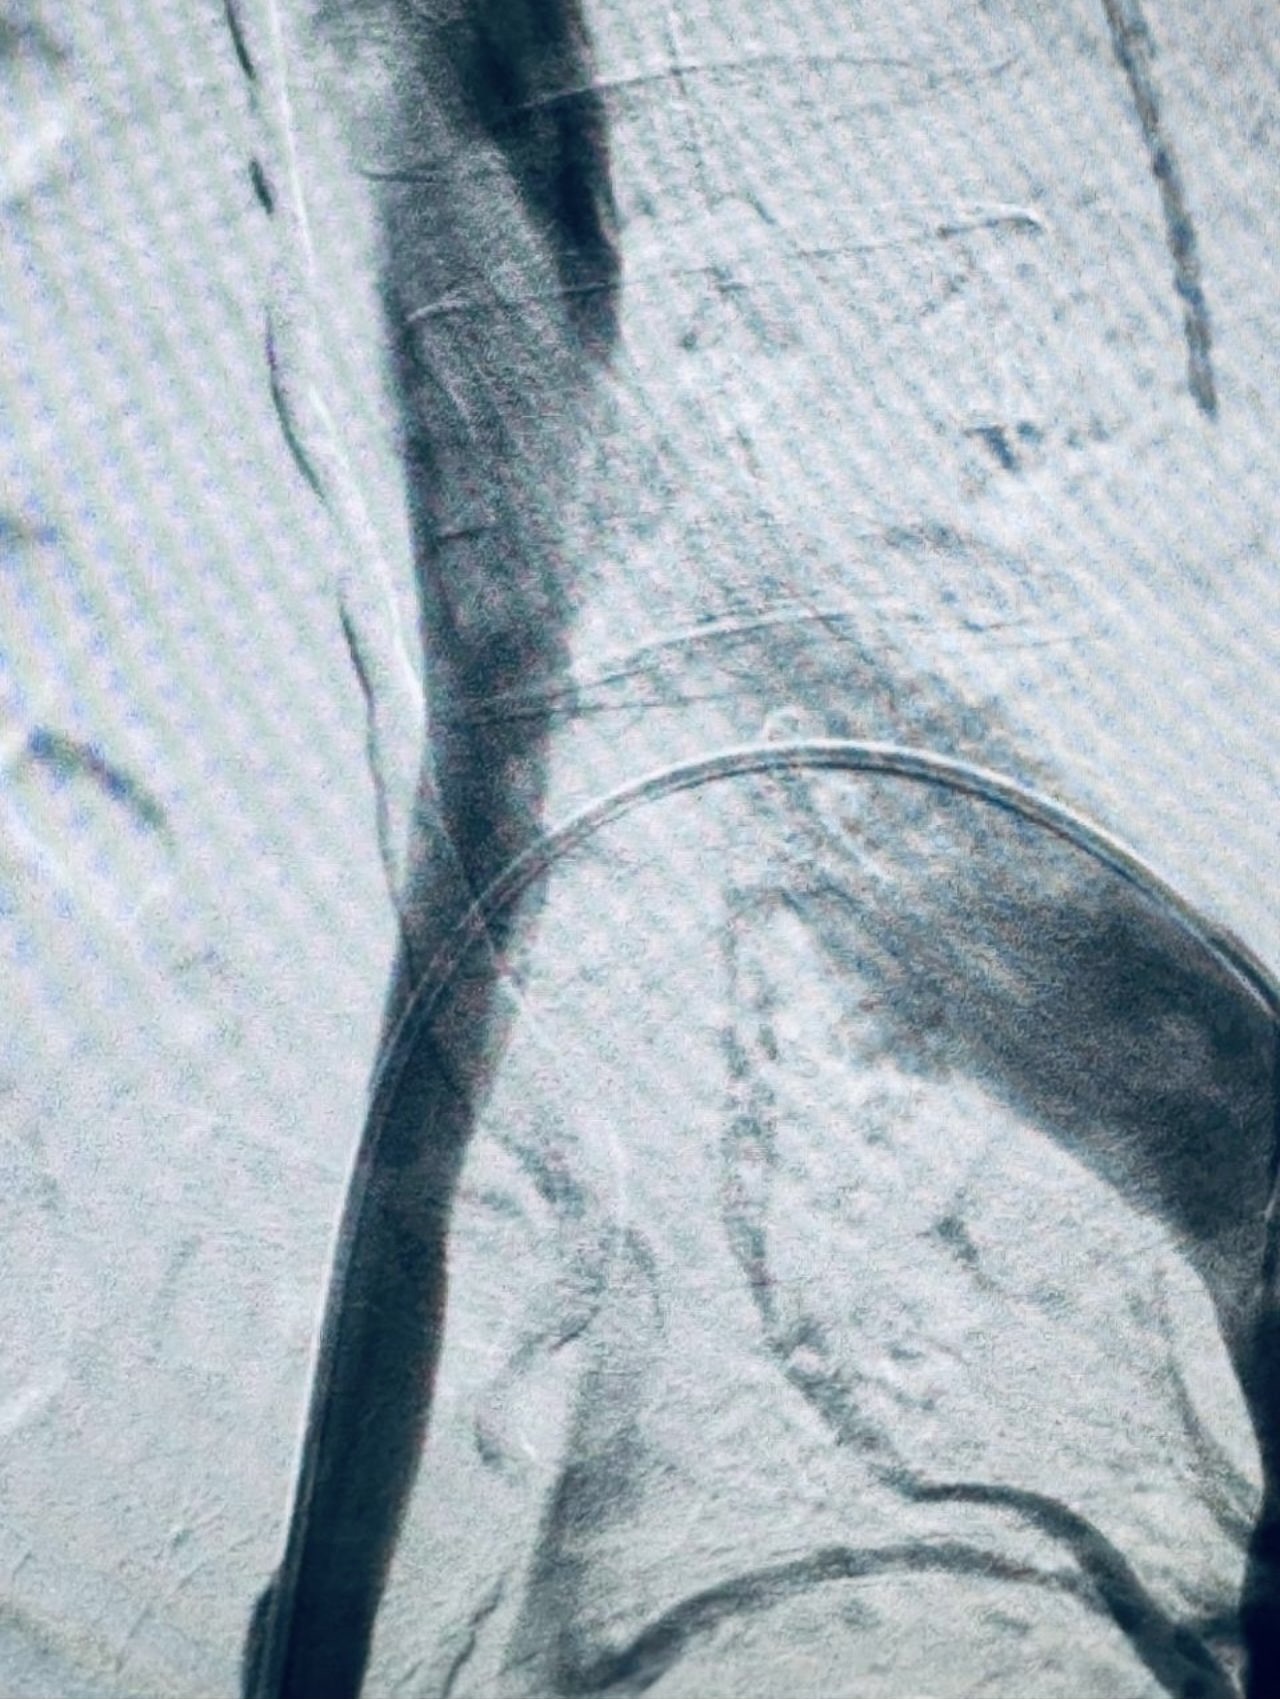

”Rapid Revascularization for Iliofemoral DVT

Acute extensive iliofemoral DVT demands a definitive solution.

The Case: Complete occlusion of the right iliac and femoral veins.

The Procedure:

1. Transpopliteal Access for direct control.

2. Mechanical Thrombectomy using the Penumbra 16 catheter for rapid clot aspiration.

3. Adjunctive Balloon Angioplasty to address underlying venous stenoses and ensure a durable result.

The Outcome: Immediate restoration of flow, resolution of symptoms, and a significant reduction in the risk of Post-Thrombotic Syndrome.

A powerful, minimally invasive approach that changes the patient’s trajectory.”